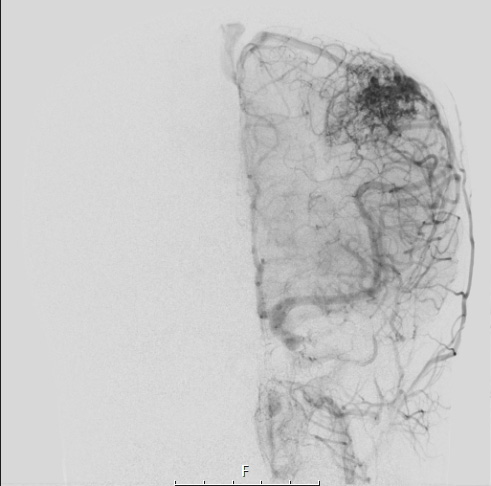

34A7 AVM, hybrid vessels (Case 34) Angiogram LCCA W - Copy

Angiograms of the vascular malformation is seen in coronal view.